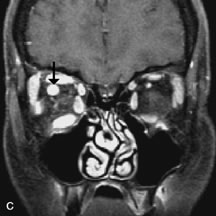

Inflammatory and Lymphoproliferative Lesions

Inflammatory conditions of the orbit, both idiopathic (inflammatory pseudotumor) and those of known causes, have been found to be hypointense to fat and isointense to muscle on Tl-weighted studies and isointense or slightly hyperintense to fat on T2-weighted images (Fig. 21).50,64,69 The more fibrous or sclerosing varieties have less signal intensity on T2-weighted images. Marked enhancement is seen in pseudotumor infiltrates after gadolinium administration.70 The same signal characteristics are demonstrated in patients with Tolosa-Hunt syndrome, with mass lesions seen in the cavernous sinuses and orbital apices.71

Fig. 21. A. T1-weighted MR scan demonstrates diffuse enlargement of both the superior rectus and levator palpebrae superioris muscles (single arrows). The involvement of the tendinous insertions and preseptal soft tissues (open arrows) as well as lack of involvement of other muscles helps differentiate this entity from thyroid-associated orbitopathy. B and C. Postcontrast fat-suppressed T1-weighted MR scans demonstrate extensive enhancement of the involved muscles as well as the preseptal (open arrows) and perinuscular tissues (double arrows).